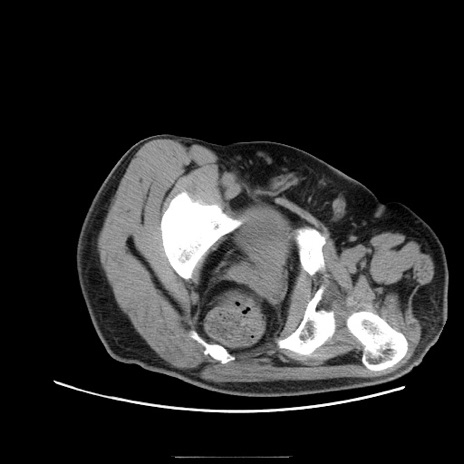

症例22(横断像)

【症例】50歳代男性

【主訴】腹痛

【現病歴】AVMからの被殻出血のため回復期リハ病棟入院中。 本日午後3時頃急に下腹部痛が出現した。

【既往歴】AVM、被殻出血、虫垂炎、高血圧

【身体所見】意識晴明、左半身不全麻痺、会話の理解は良好、36.5°C、腹部:膨隆、全体に板状硬、下腹部正中に圧痛点あり、反跳痛-、筋性防御不明、右下腹部にope scar

【データ】WBC 9400、CRP 0.06